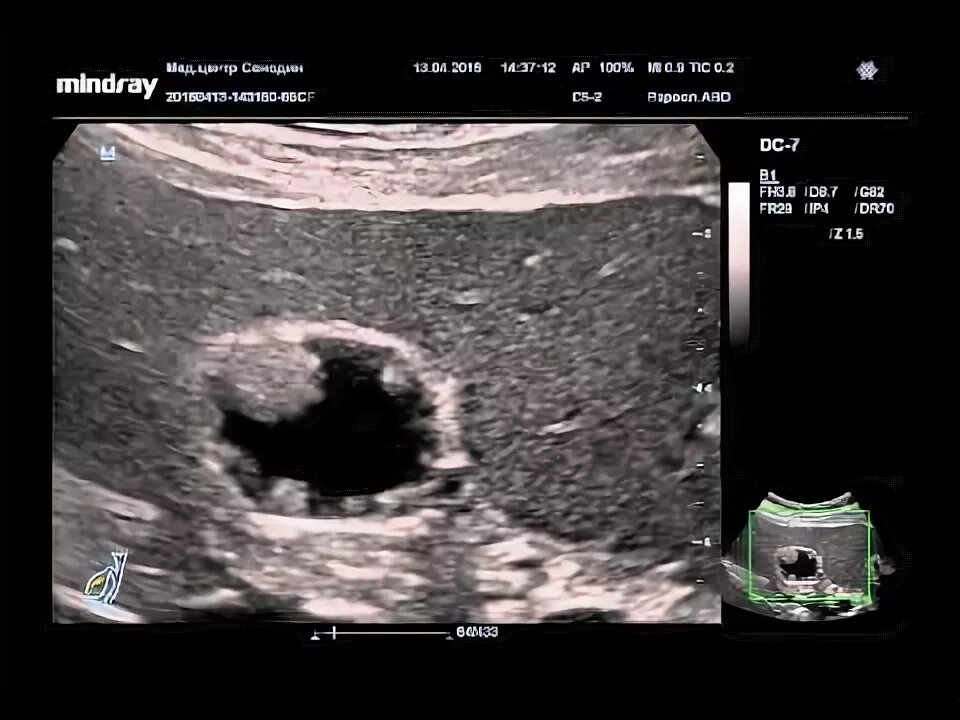

Удаление полипов желчного пузыря операция